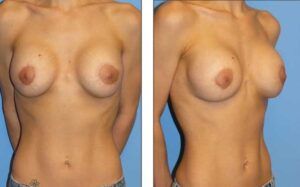

This is a patient who had asymmetrical implants, with the right one being higher than the left.

Dr. Agha performed a revision procedure that lowered the right implant, releasing the lower aspect of the implant pocket and the inframammary fold.